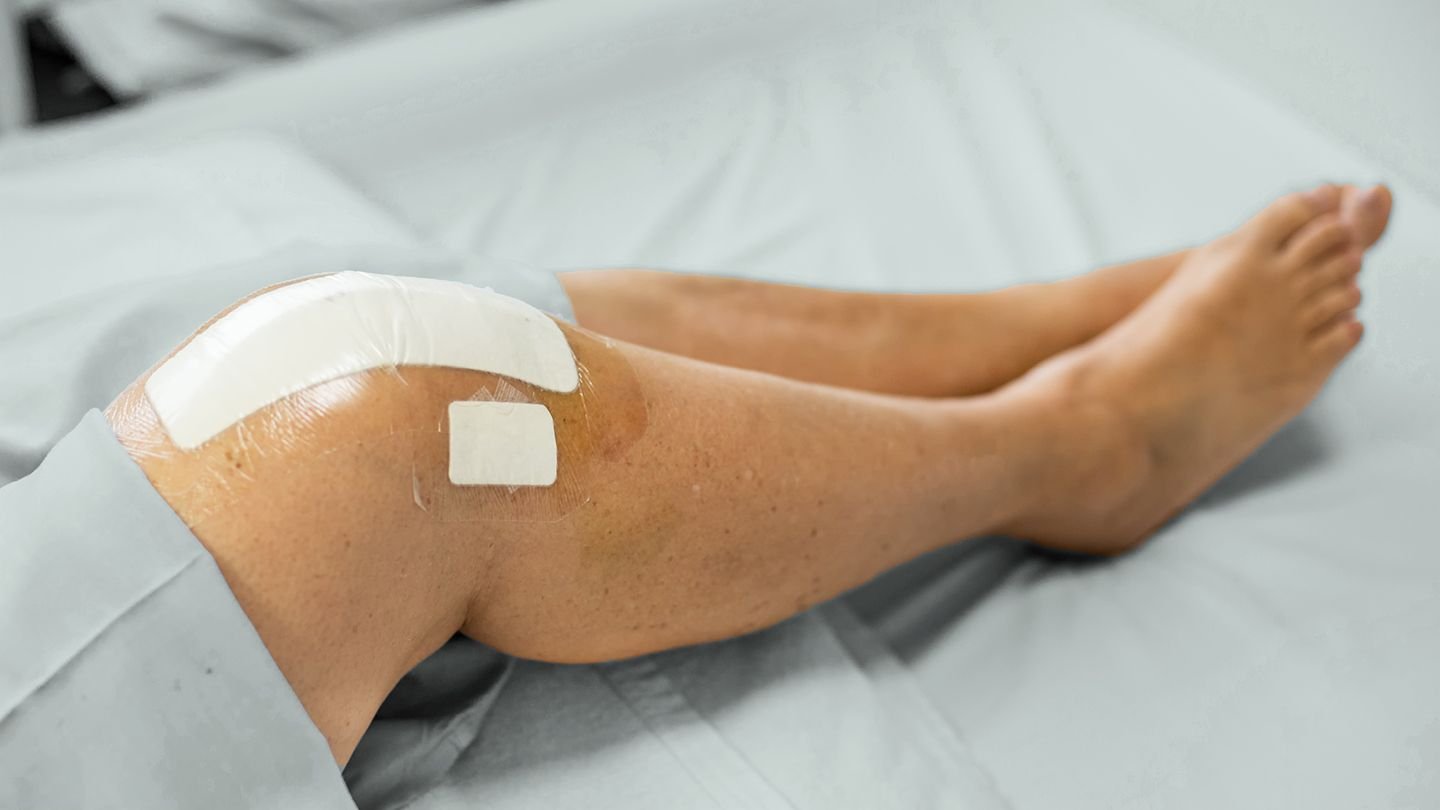

Harnessing cutting-edge robotic technology and evidence-based techniques, we provide highly precise joint replacement and sports injury treatments designed for quicker recovery, reduced pain, and long-lasting results.

Sports Injury Rehabilitation and Ligament Reconstruction focuses on restoring joint stability, strength, and function

Comprehensive management of sports injuries includes ligament reconstruction and guided rehabilitation protocols.